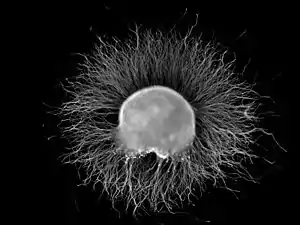

A dorsal root ganglion (DRG) from a chicken embryo (around stage of day 7) after incubation overnight in NGF growth medium stained with anti-neurofilament antibody. Note the axons growing out of the ganglion.